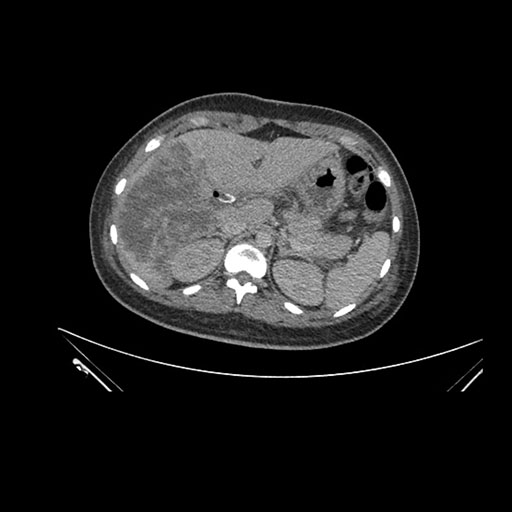

Imaging Analysis

Look through the patient's CT scan to identify any areas of concern for the necessary procedure.

Axial Arterial

Based on initial findings, which issue(s) would you be most concerned about?